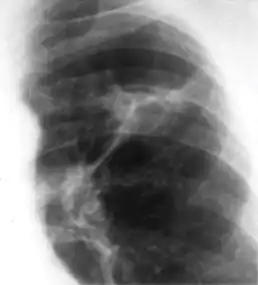

Chest x-ray showing coarse reticulonodular densities on the lower right lung of post-primary pulmonary TB.